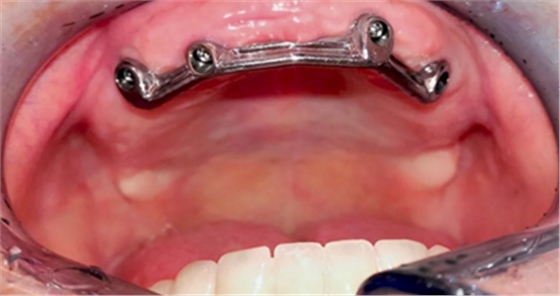

在下次就診時,檢查切削研磨后 Dolder 桿卡的就位,及密合度,防止種植體間的張力,確保新義齒有最佳的適合性(圖 10)。

(圖10)